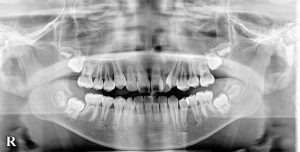

新着情報 600_20180816_1630_① Tweet 投稿日 : 2020年02月13日(木)カテゴリー : コメントを残す コメントをキャンセルメールアドレスが公開されることはありません。 * が付いている欄は必須項目ですコメント 名前 * メール * サイト 12歳 男性 「 八重歯 ガチャガチャ を治したい 」 ( 抜歯症例 ) ≫